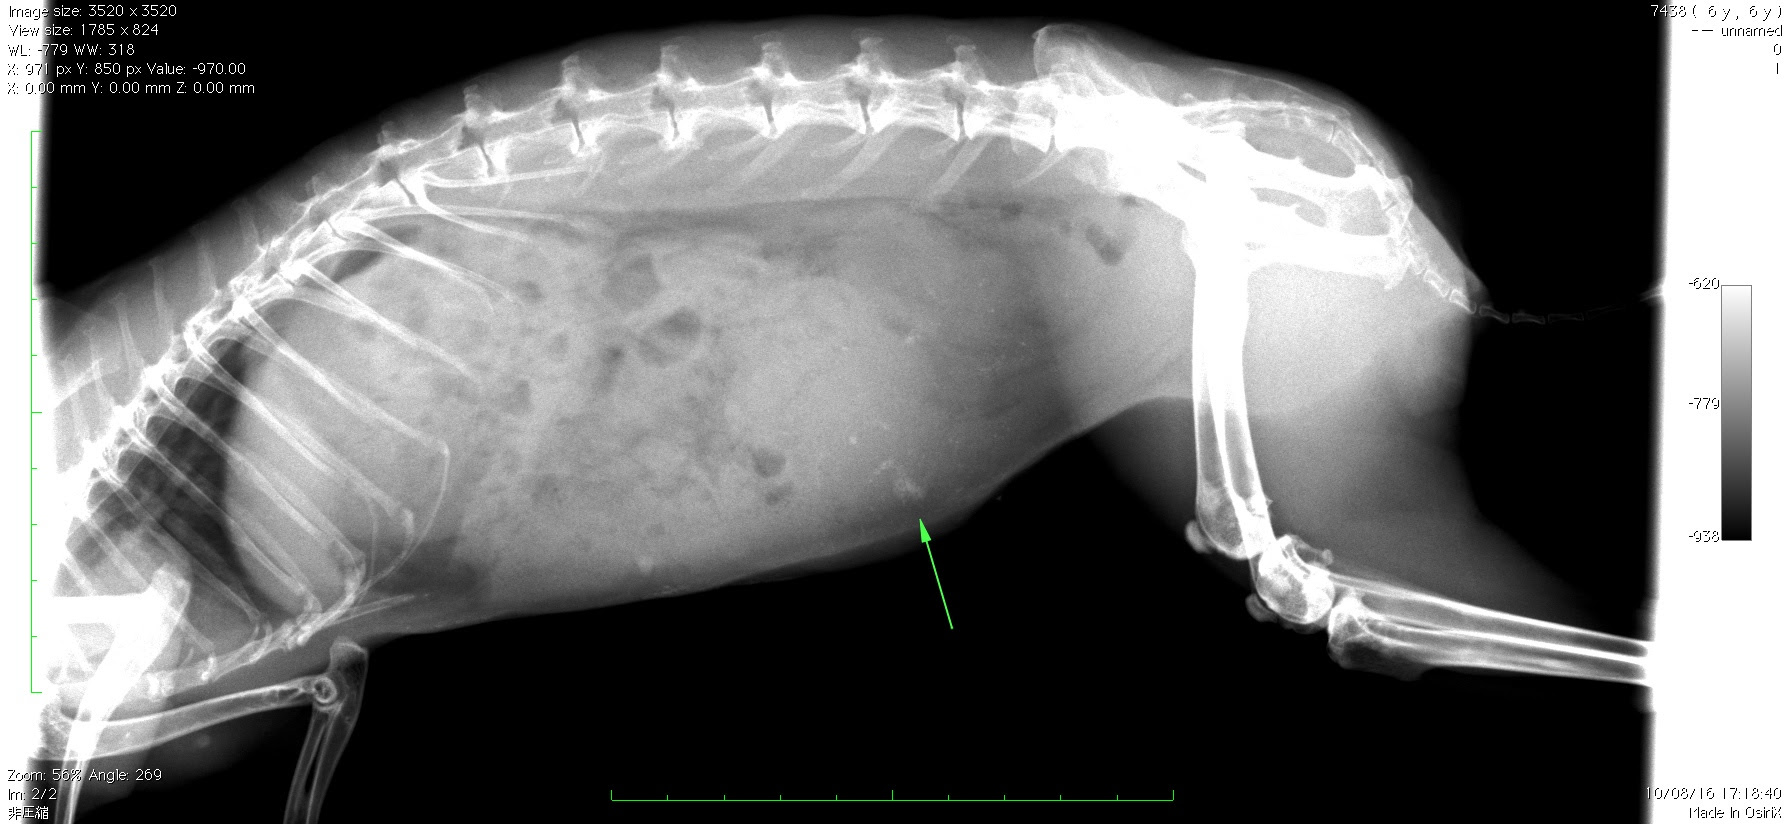

うさぎ 子宮 病気-ウサギの子宮疾患 ウサギの寿命は以前は67歳くらいと言われていました。 しかし、最近では10歳以上生きるウサギも増えてきており、高齢のウサギは雄か避妊された雌がほとんどです。 この原因 子宮癌は以下のようなさまざまな症状が出ます。 しかし病気が進行しないと症状が現れないため、早期発見が難しいのが現状です。 (1) 血尿、陰部からのおりもの・出血 (2) 元

うさぎに良くある病気で皮膚病があります。 背中やわき腹のあたりに「いぼ」ができたり、皮膚が荒れて毛が抜けたりします。 ダニなどが原因で皮膚病になることもあります。 う メスの生殖器疾患の割合 メスうさぎ まず、うさぎのメスをお迎えするときに知っておいてほしいのが子宮の病気。 子宮ガン、内膜増殖症、水腫などが手術をしていないメスのうさ